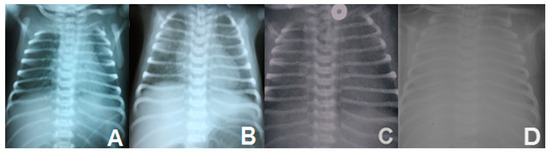

3.1.2. Biologic, Imagistic Assessment and Treatment

| 10. | Ognean et al., 2024 (this study) | Male | 37 weeks | 2700 g | Severe nRDS—advanced respiratory support (HFOV), prednisone, azithromycin, hydroxychloroquine treatment | Thoracic X-ray—ground glass homogeneous opacity | CPI pattern with lobular remodeling, prominent AEC II hyperplasia, focal PAP pattern, and extensive DIP-like areas; alveolar proteinosis | N/A | p.Arg280Cys (R280C, c.838C>T, rs201299260)/heterozygous/paternal origin | p.Gln233ter (Q233X, Q233*)heterozygous/maternal origin | SFTPB p.Val267Ile | No, healthy parents, one healthy sibling despite carrying p.Gln233ter and SFTPB p.Val267Ile variants | Died at 77 days of life | Current case report |